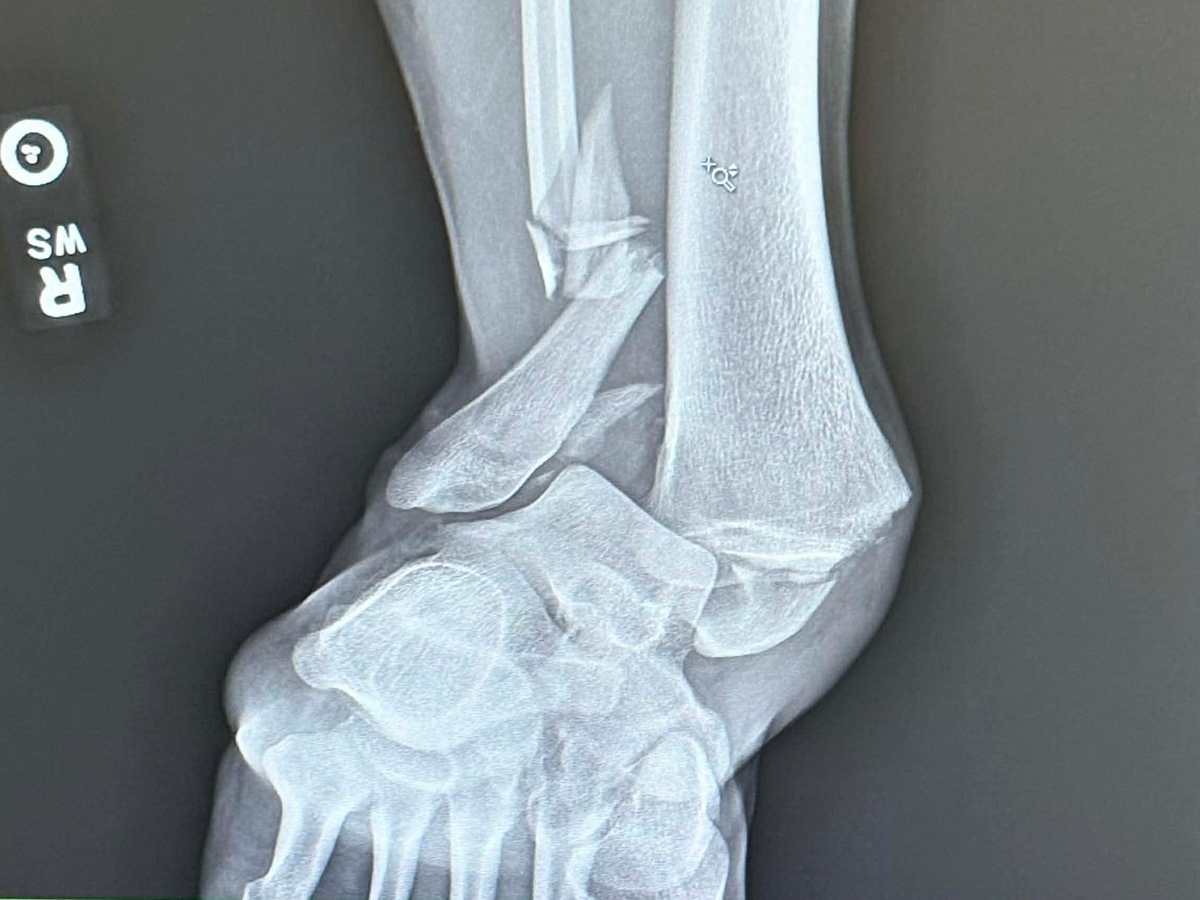

Ended up losing traction while driving in the snow and hit a tree. I broke my tibia, fibula, and ankle bone, gashed my eyebrow open (needed six stitches), broke some ribs, and bruised both lungs.